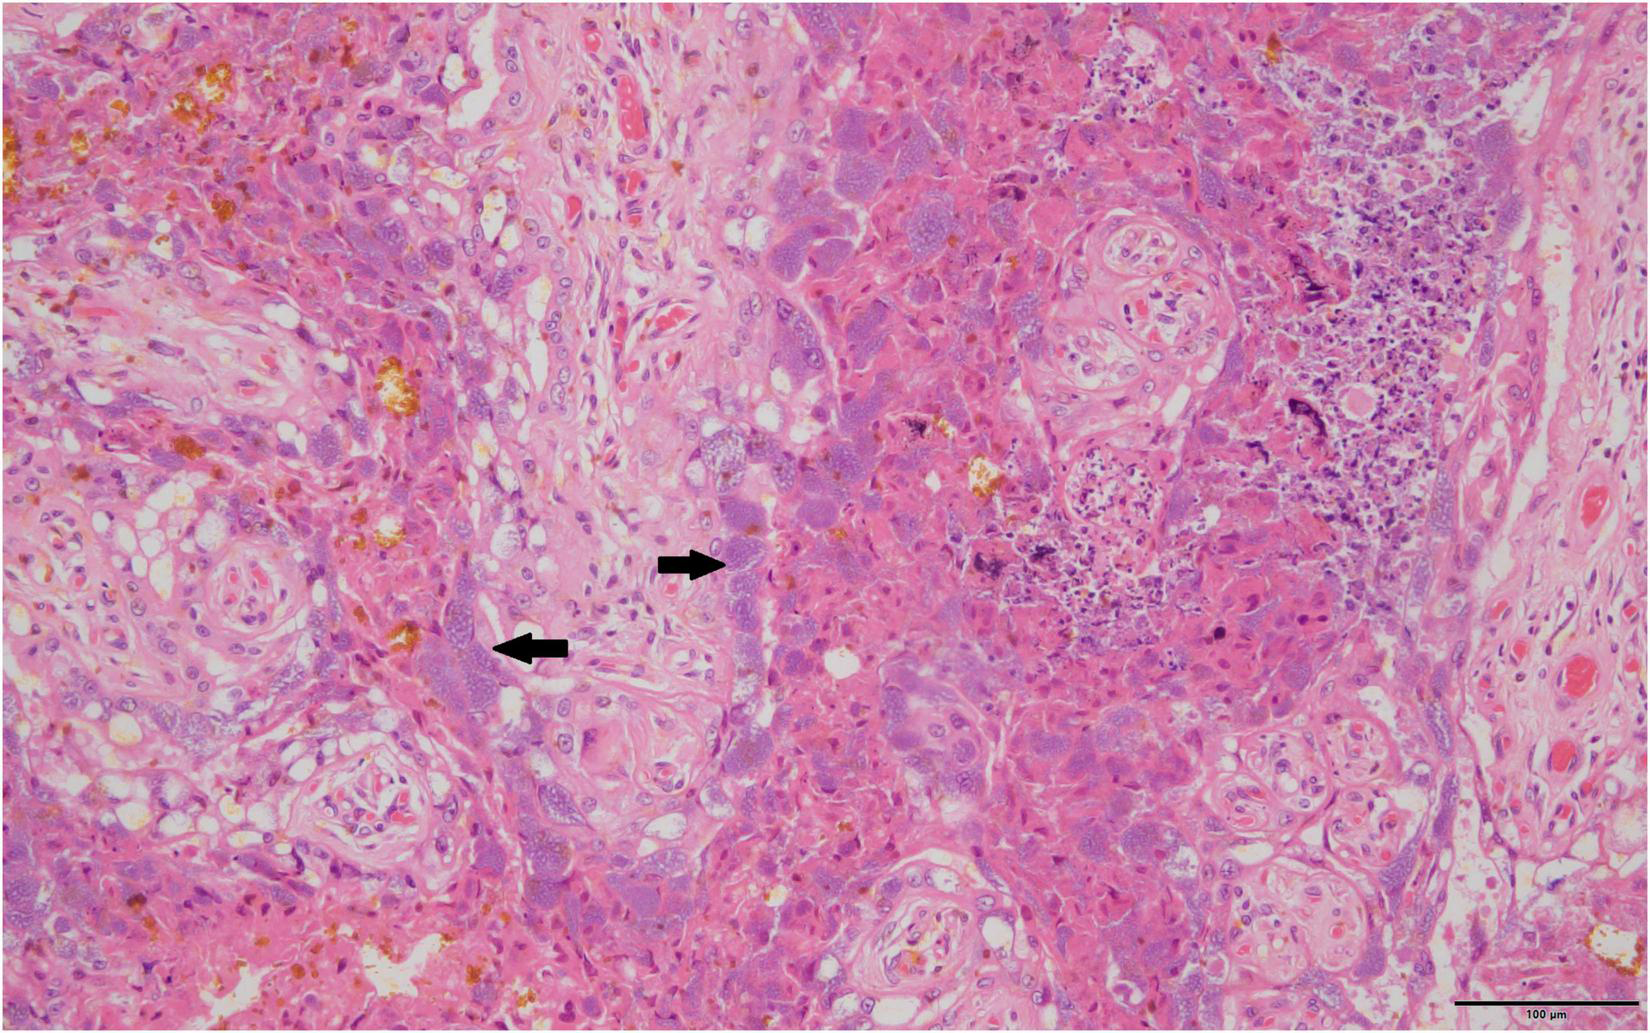

Routine histopathology did not show any Cb organisms in any of the aborted fetal material including the associated aborted placentas. There were various non-specific lesions present throughout the fetuses, but none were positive for Cb. Amnion aspiration was commonly detectable through the presence of increased numbers of squamous epithelial cells present in the alveoli of the fetal lung and present in 29.8% of aborted fetuses. Nearly a fifth (23.4%) of the fetal lungs had what appeared to be histiocytic pneumonia with occasional neutrophilic infiltrates. There were non-specific cardiac lesions in 14.9% of the aborted fetuses including lymphohistiocytic epicarditis, regional myocarditis and myocardial necrosis. Of all the full-term placentas examined histologically on routine hematoxylin and eosin staining, intracytoplasmic bacteria were only detectable in one sample. The organisms were not uniformly distributed, but when present formed stippled cytoplasmic inclusions with characteristic foamy appearance within the placental trophoblasts (Figure 1). The Cb organisms did not appear to be associated with significant inflammatory reactions.

FIGURE 1

Typical foamy Coxiella burnetii cytoplasmic inclusions within the placental trophoblasts are indicated by solid black arrows, 40×, hematoxylin and eosin stain.